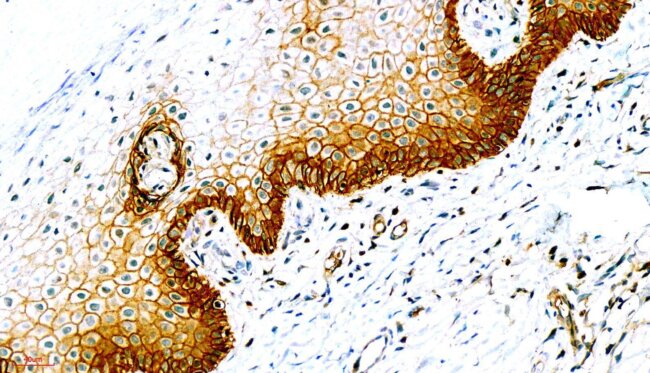

IHC染色

By

立众小編1號

2021-07-01